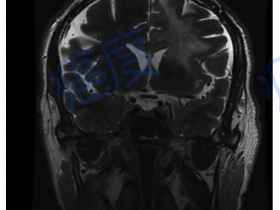

脑癌复发患者从瑞戈非尼治疗获益 EGFR基因突变

脑癌复发患者从瑞戈非尼治疗获益

脑癌的治疗一直是难题,突破不多。而一款靶向药的出现,带来了一线曙光。 多形性胶质母细胞瘤的一线治疗 多形性胶质母细胞瘤(GBM)是中枢神经系统最为常见、最具有侵袭性的恶性肿瘤之一,占所有...